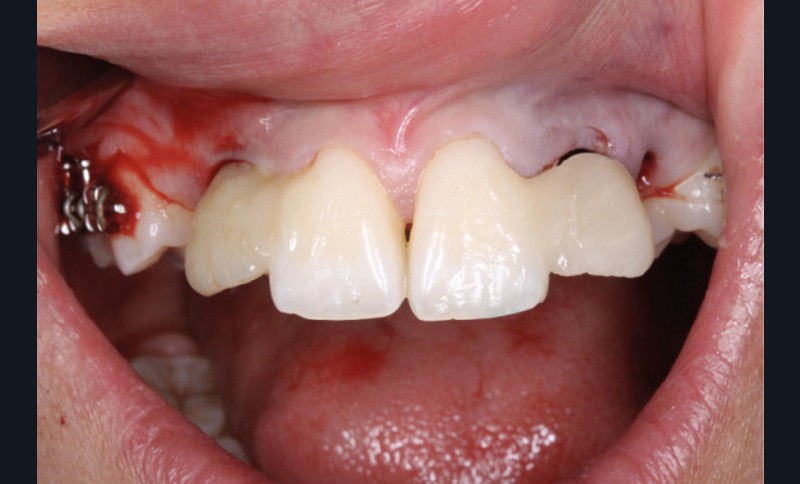

Les extractions de 12, 22, 63, 34 et 44 ont été réalisées dans un premier temps. Un cache esthétique en résine composite a été élaboré à partir d’une clé en silicone obtenue sur les empreintes initiales et collé sur 11 et 21 afin de limiter l’impact psychologique de telles extractions (fig. 2a-b).